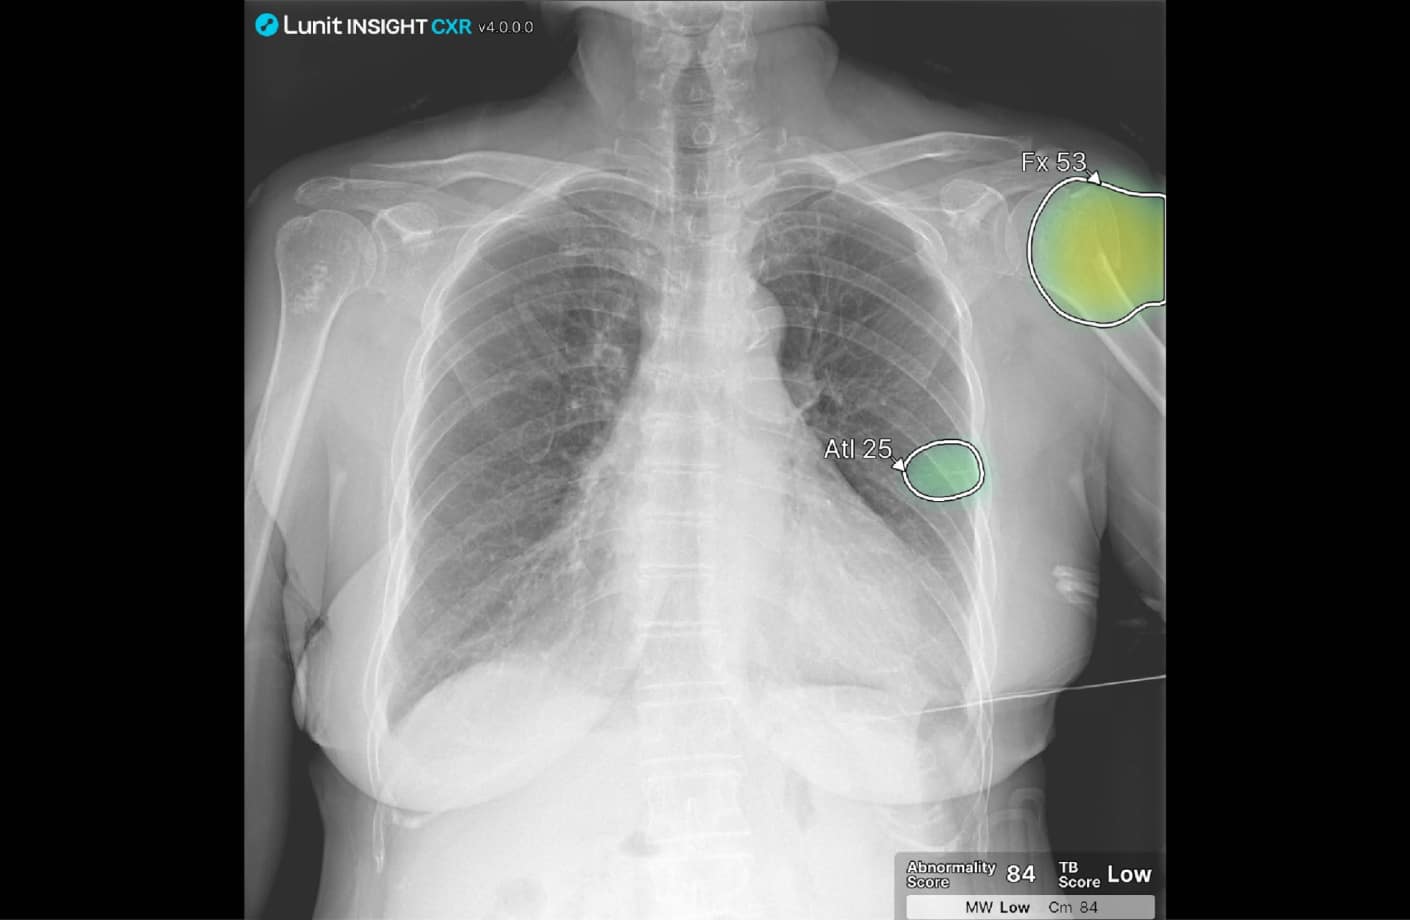

Boost precision across readers with AI that highlights 11 major thoracic abnormalities with 95-100% AUC* (and supports tuberculosis screening), compares priors, and supports earlier diagnosis.

Lunit INSIGHT CXR is a clinically validated X-ray AI solution for your entire CXR pathway. It integrates seamlessly with current workflows and assists radiologists in identifying both common and complex pathologies with greater speed and precision.

Lunit INSIGHT CXR achieves up to 100% accuracy* in detecting 11 major thoracic abnormalities—including nodules, pneumothorax, consolidation, pleural effusion, and fractures. Its performance has been independently validated on more than 250,000 chest X-rays.